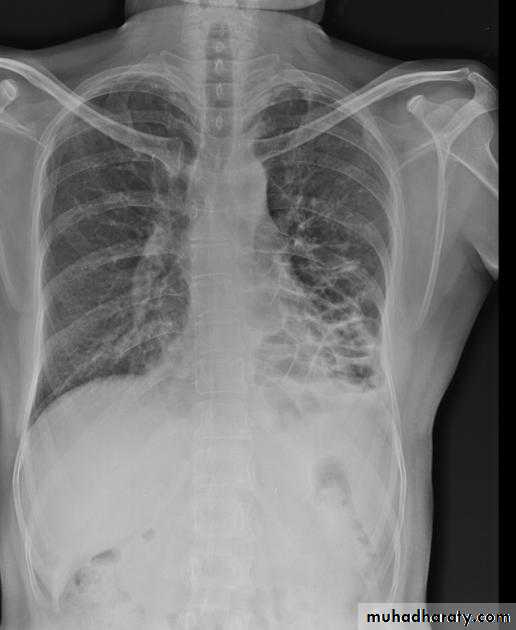

Lobular consolidation ( broncho pneumonia )

Very important to consider that pulmonary edema in normal sized heart have close similar appearance to broncho pneumonia

The important Golden Key differentiation is the cardiac size being enlarged in pulmonary edema .

36.lobuler consolidation (lobular pneumonia )37.discussion